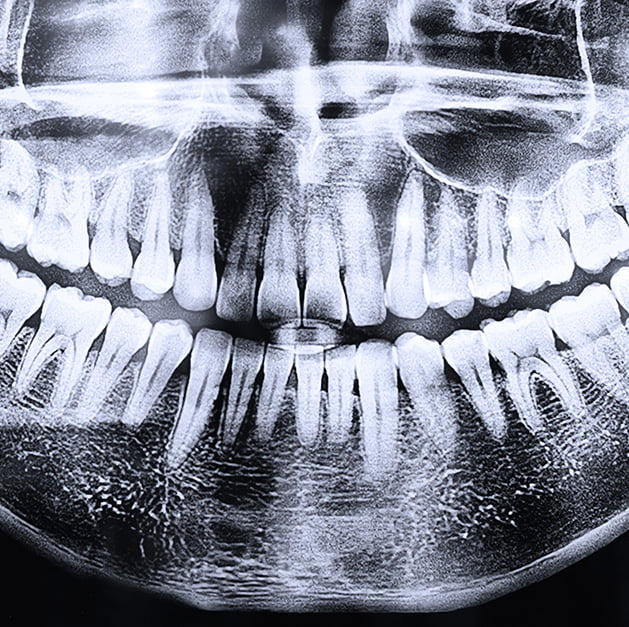

Trauma, infection, tumors

congenital conditions

surgical conditions of teeth or maxillofacial region

Impacted teeth, carious lesions

periodontal or periapical pathology

Missing or crowded teeth

TMJ views and assessment

Sialolithiasis